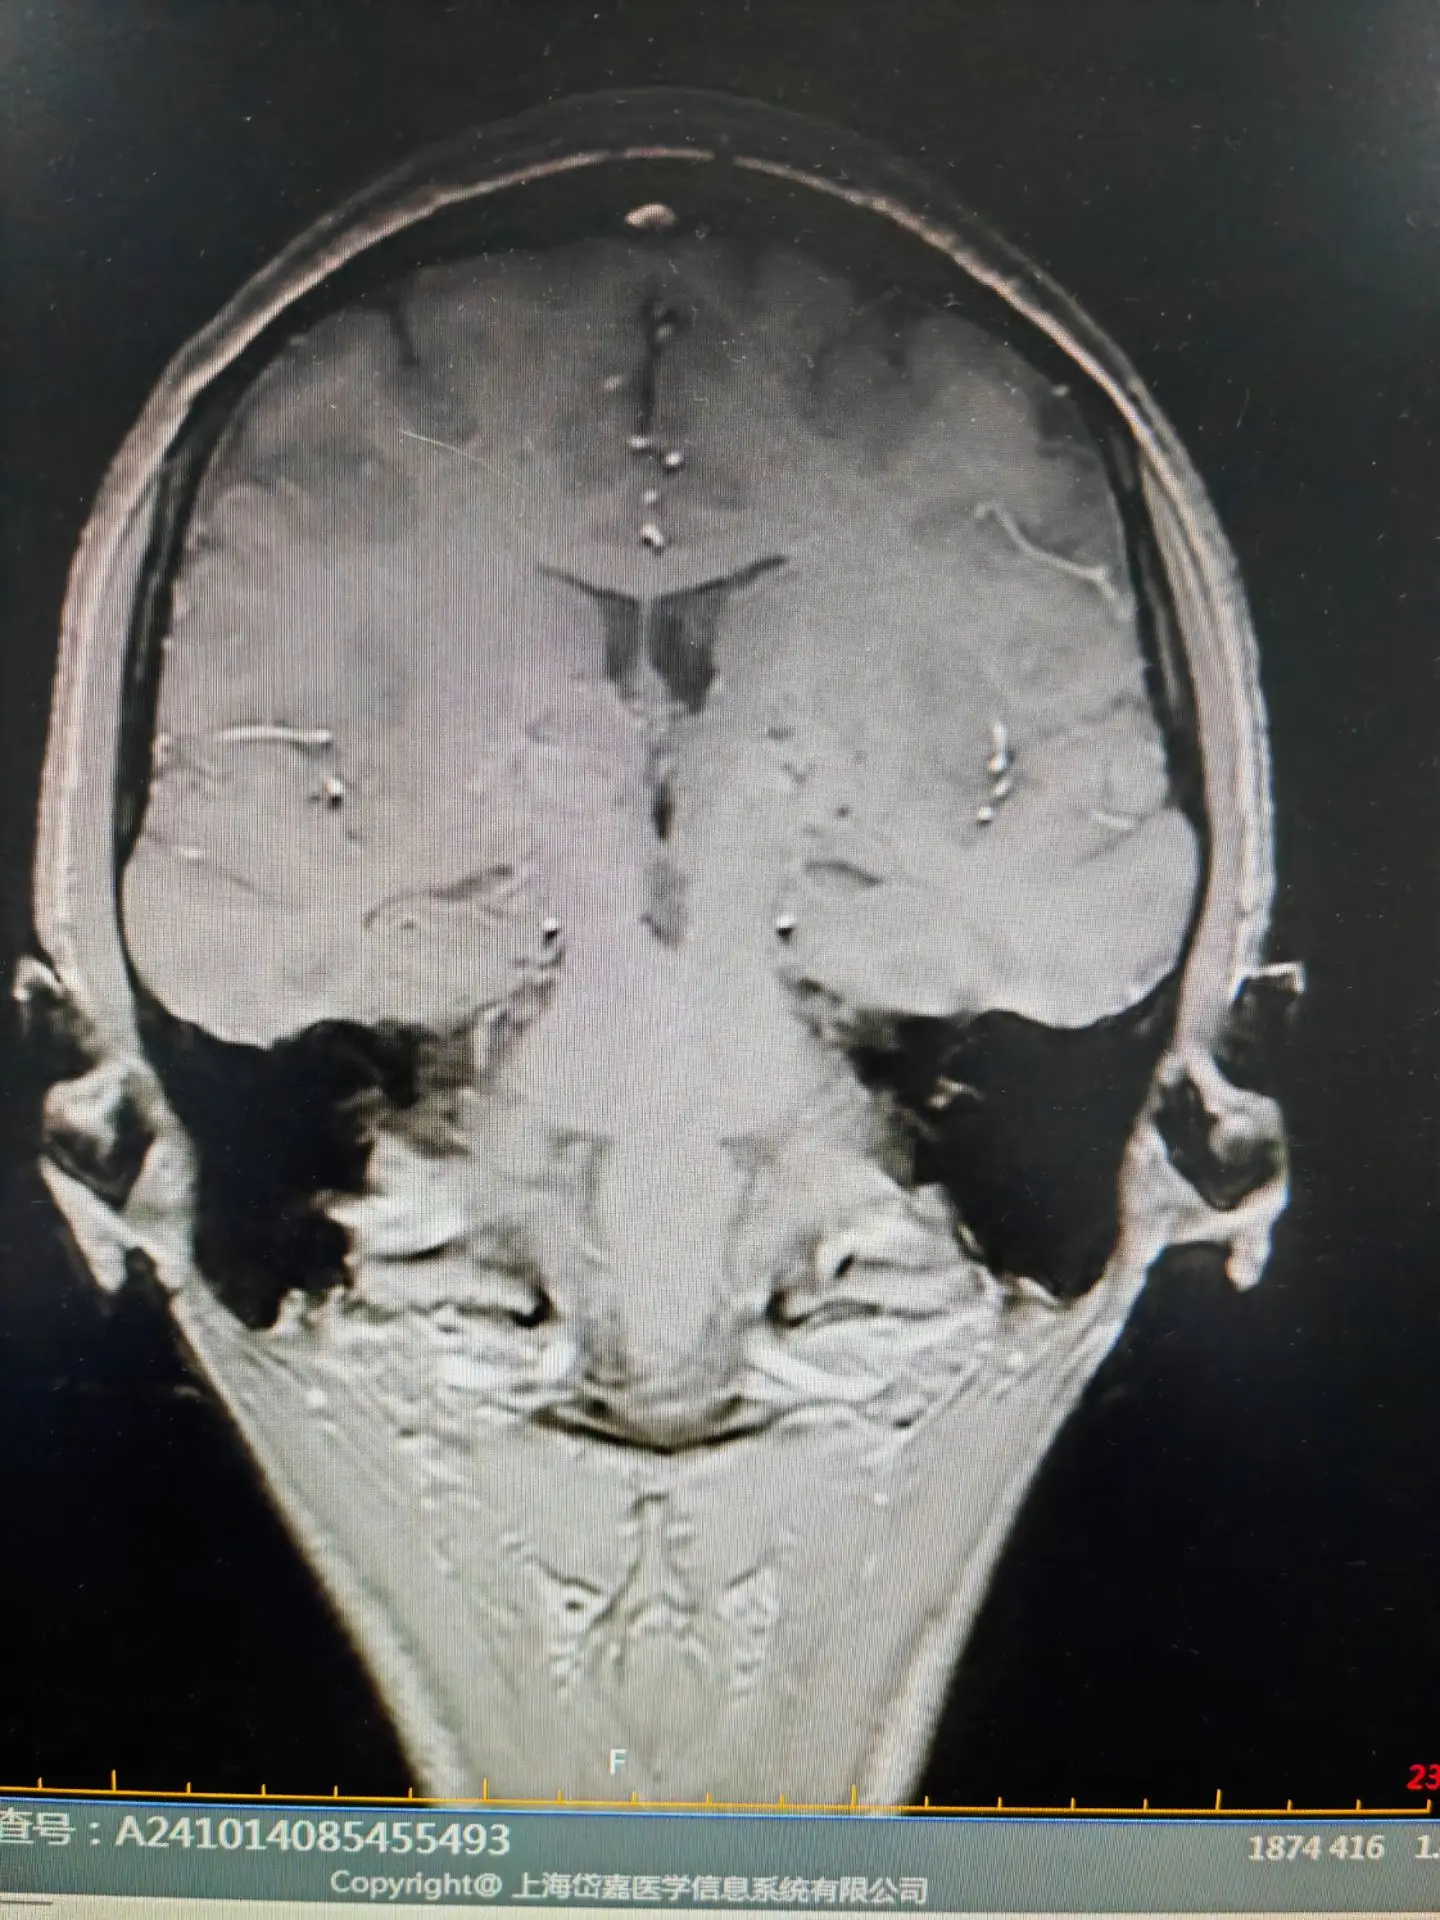

脑铁沉积病—虎眼征👁。脑铁沉积病目前发现有10种不同的基因遗传相关的神经系统退行性疾病,常伴有基底节区的铁沉积,其中有7种脑铁沉积病可表现为PPS。尤其最为常见的PANK2基因突变引起的泛酸激酶相关性神经退行性疾病,青少年起病,首发症状可表现为帕金森样表现,合并锥体束征和认知精神障碍,头核磁可表现为典型的“虎眼”征。脑铁沉积病的患者其帕金森症状对于左旋多巴类药物反应较差或无反应,头核磁表现为不同程度的铁沉积是鉴别的要点。虎眼征